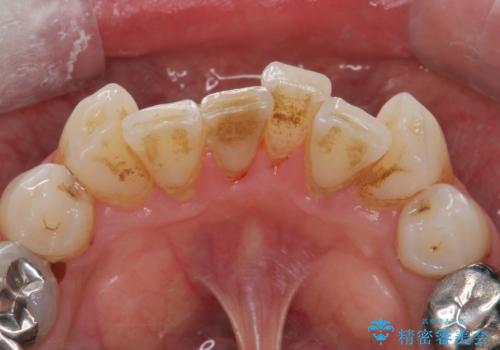

着色が気になる。

- 着色が気になるとの事で来院。

PMTC30分コースを行いました。